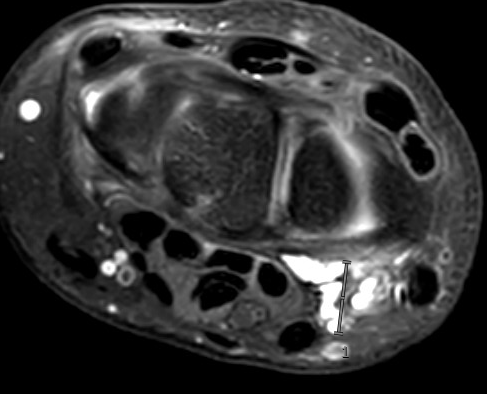

Volar ganglion with radial artery superficial to ganglion

Volar ganglion